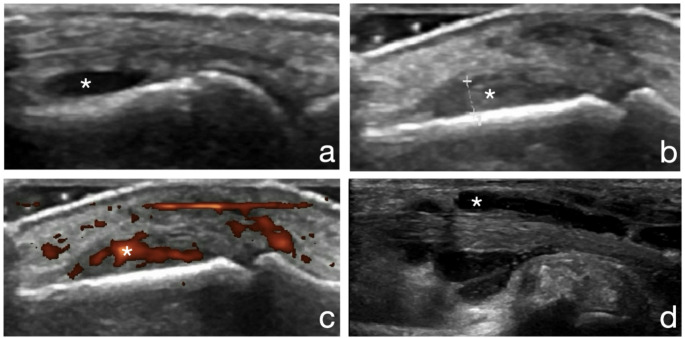

Methods: Disease activity was evaluated in 61 RA patients, with clinical indices and ultrasound (hands and wrists). Bone mineral density (BMD) and architecture were analyzed with HR-pQCT and DEXA.

Results: Ultrasound RA disease activity parameters [synovitis, power doppler (PD)-positive joints, sum of positive power doppler signals and tenosynovitis] were associated with altered HR-pQCT bone density and structure at tibia or radius (trabecular volumetric BMD, trabecular bone volume fraction, trabecular thickness and cortical porosity). In addition, wrist ultrasound activity was specifically locally associated with impaired local bone microarchitecture at distal ipsilateral radius. Clinical and functional RA disease activity parameters (number of swollen joints, Health Assessment Questionnaire and disease activity score DAS28-CRP) were also correlated with HR-pQCT parameters (total and trabecular volumetric BMD, trabecular thickness and cortical thickness). At the hip, BMD correlated with VAS-fatigue and DAS28-ESR. The number of synovitis detected by ultrasound was higher when total hip T-score was lower than - 1.

Discussion: Ultrasound and clinical disease activity parameters were associated with impaired HR-pQCT parameters (distal radius and tibia), with lower trabecular and cortical bone densities and impaired bone microarchitecture (organization of spans and cortical porosity). In addition to systemic contribution to bone impairment, a local correlation between wrist US activity and HR-pQCT at distal radius was observed.